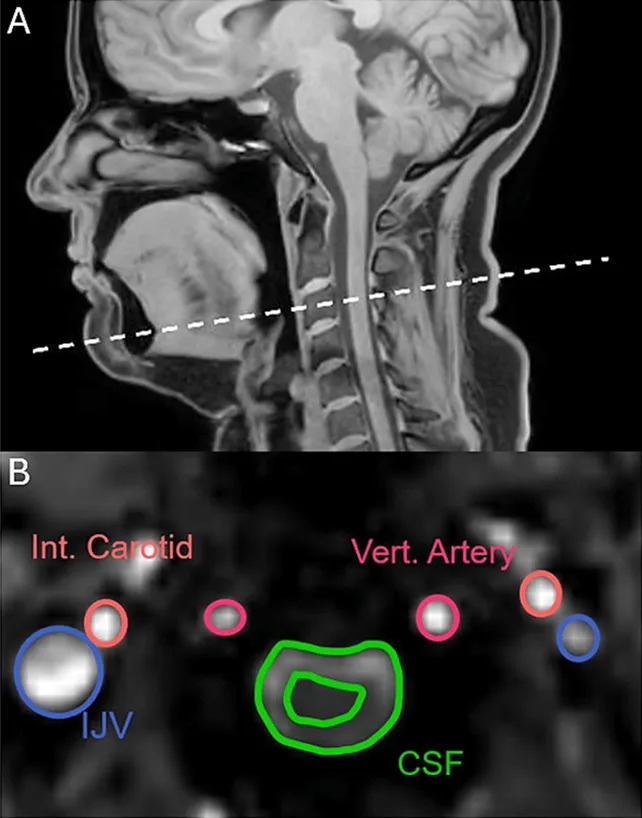

The research team scanned the heads and necks of 22 healthy volunteers using MRI while participants were instructed to yawn, take deep breaths, suppress yawns and breathe normally. The researchers compared the mechanical and hemodynamic effects of yawning versus deep inhalations.

CSF Movement: Yawns produced a detectable displacement of cerebrospinal fluid away from the brain — a pattern not seen with deep breaths.

Blood Flow: Both yawns and deep breaths increased venous outflow from the brain, which can create space for fresh arterial blood to enter. During the early phase of a yawn, carotid arterial inflow surged by roughly one-third.